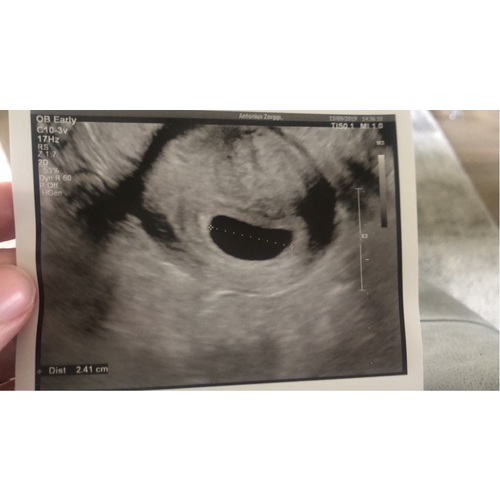

Bij de normale echo op de buik zag ik precies hetzelfde bij 5 weken (een lege baarmoeder) . En daarna de inwendige geprobeerd, toen zagen we het wel. Dus misschien is het te klein voor om op beeld te komen?

Bij de echo alleen een leeg vruchtzakje te zien.

Daarom kregen wij al snel een echo (inwendig) en was er ook alleen een vruchtzakje te zien.

Toelichting van de echoscopiste was dat het mogelijk is dat het vruchtje te klein is en nog iets te hoog ligt om inwendig te kunnen zien.

Op de uitwendige echo was het heel goed te zien.